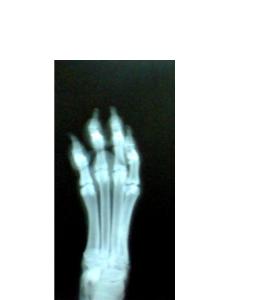

X-rays are used by us to visualize what

is going on inside your best friend.

The

radiograph machine gives us this

picture immediately.

This is an image of a normal

canine foot.